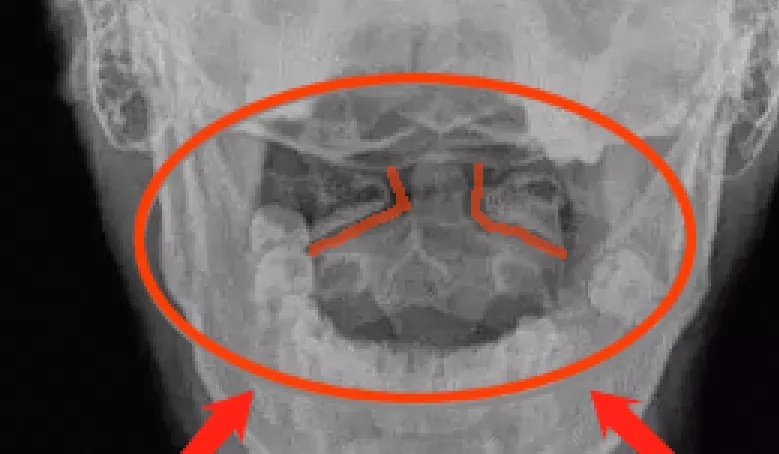

触诊检查发现,她的颈1横突偏歪,X光片显示寰齿侧间隙左右不等宽;颈1、2关节间隙不平行,颈2、5、6棘突偏歪,有压痛。

X光片开口位,寰齿侧间隙不对称

① 开口位片见寰椎双侧的侧块不对称,寰齿侧间隙及寰枢关节间隙左右不对称,枢椎棘突偏歪。